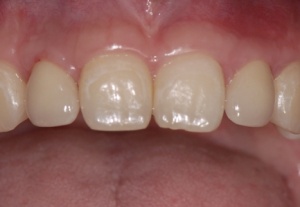

Die Einheilzeit für die Implantate beträgt drei Monate. Anschließend erfolgt die Freilegung und prothetische Versorgung der Implantate. Die Freilegung erfolgt bei einem Implantatsystem mit konischer Innenverbindung (Astra Tech, Mölndal, Schweden) durch eine kleine Stichinzision und Verdrängen der Schleimhaut durch Eindrehen der Gingivaformer. Die keratinisierte Gingiva bleibt somit vollständig erhalten. Ein kurzzeitig auftretendes anämisches Gebiet ist hierbei für den Heilungsverlauf unbedeutend. Nach etwa einer Woche können die Implantate prothetisch versorgt werden. (Abb. 20–25)